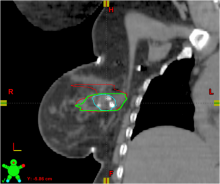

PET-CT | December 04, 2020

This is an example of Canon's Advanced intelligent Clear-IQ Engine (AiCE) AI-driven image reconstruction software that is now being used to improve image quality on the Canon Celesteion Prime PET/CT nuclear imaging system. The deep learning is used to enhance the iterative reconstruction used to reduce noise and sharped high contrast resolution on positron emission tomography (PET) images from the digital PET detector used on the system.

This example is a whole-body FGD PET scan of a patient with a large BMI with lung cancer.

The Cartesion Prime PET/CT is the industry’s only air-cooled digital PET/CT, provides variable bed time (vBT) acquisition as a standard feature. This and the new FDA 510(k)-pending AiCE technology were highlighted at the 2020 Radiological Society of North America (RSNA) virtual meeting.